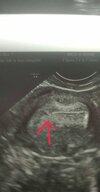

Hej Kochane, dzisiaj 35dc, wyszla cienka kreska. Czy moge aie cieszyć czy macie jakieś zle doświadczenia taka kreska? Powinna byc gruba i bardziej widoczna? Cykle nieregularne.. Okropny bol piersi az mnie poli pod pachą i bol w dole plecow.

Ciąża jak nic😉 Mnie zawsze jeszcze słabsze wychodziły, tylko ja je widziałam🙈 Wszystko jest ok, ciąża jest jeszcze mała. Zrób w pn i śr betę i sprawdź jak przyrasta. Gratulacje!!!